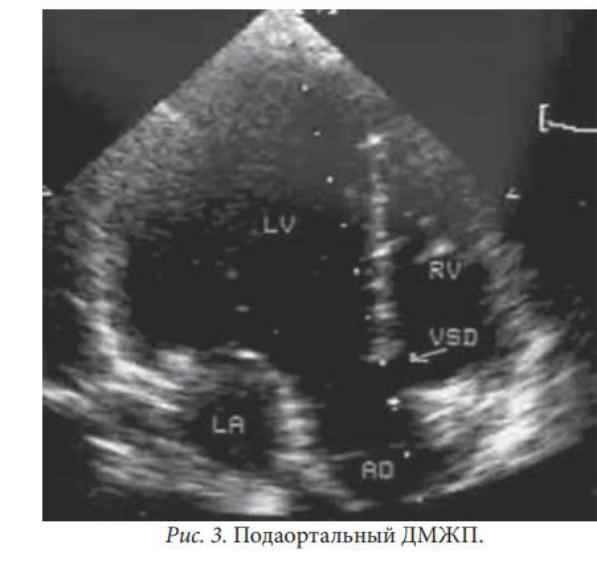

Высокий подаортальный дефект межжелуждочковой перегородки: